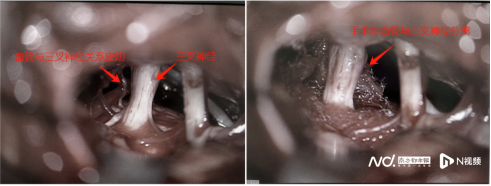

“三叉神经痛虽不会危及生命,却非常顽固,对患者的生活和精神影响极大。”欧阳辉教授介绍,三叉神经是头面部的主要感觉神经,主要负责面部的感觉传输,当这条神经受到压迫或病变时,会引起“短路”,引发刀割样、电击样、烧灼样、撕裂样剧痛。这种痛被喻为“天下第一痛”。此时,唯有行微血管减压术把连线“短路”的血管和神经分开,才能解除故障,从病根上治疗该病。

5月上旬,该院神经外十科团队为患者行微血管减压术。欧阳辉教授提醒,如果出现类似“牙痛”症状,到牙科治疗后无法缓解,要考虑三叉神经痛的可能,及时治疗。“痛的时间越久,手术效果越难明确。”幸运的是,罗芳在术后没再“牙痛”,18年的剧痛终于一朝解除。